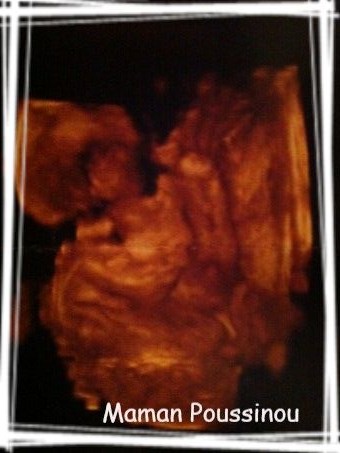

Et puis, à un moment, alors que nous regardions sa petite frimousse, le Dr Gygy, sans nous prévenir, a fait un « tour de magie » : il est passé en mode 3D… Et là, nous avons cru remarquer que son petit profil était déjà semblable à celui de son grand frère ♥

Bon je sais que c’est assez difficile de voir quelque chose, mais je n’ai pas pu résister à l’envie de la mettre…

J’avais justement un article sur l’écho 3D en préparation, dans lequel j’expliquais pourquoi nous avions décidé de ne pas en faire… mais là, j’avoue que je suis sous le charme de cette « photo » de mon beau bébé. Même si au départ, je ne voyais absolument RIEN ! Ca a duré moins de 5 minutes, le temps d’essayer de lui faire déplacer ses petits pieds et petites mains de devant sa petite tête pour que nous puissions bien le contempler… en vain, c’est déjà un petit coquin !